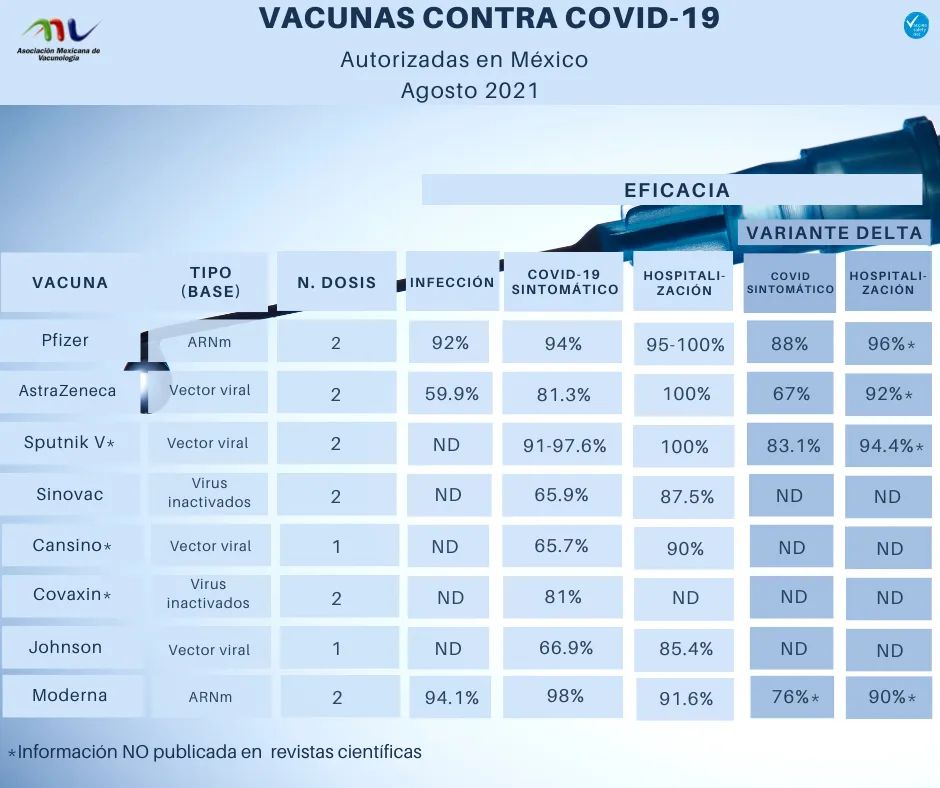

Todas las vacunas contra COVID-19 ofrecen alto porcentaje de protección: Asociación Mexicana de Vacunología

Rossana Luna Cerdán, 18 de agosto de 2021

Investigan eficacia de vacunas anticovid aplicadas en México sobre nuevas variantes del virus SARS-CoV-2

Mahaleth Guevara Alamilla, 10 de agosto de 2021